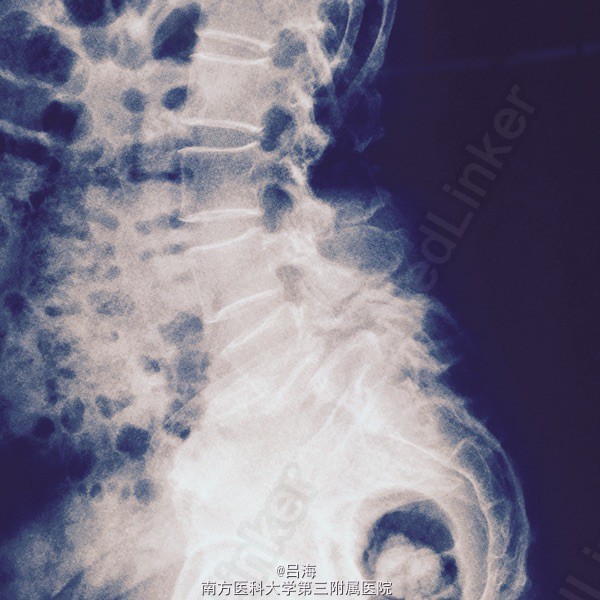

腰痛伴双下肢麻痛无力3年,加重1周。腰椎活动受限,弯腰时明显,间歇性跛行。

下腰压痛,并向双下肢放射,直腿抬高试验阴性。 腰椎DR,CT提示:腰5椎体二度滑脱并峡部裂,椎管狭窄

腰5椎体II度滑脱并峡部裂;椎管狭窄症。 后路腰5全椎板切除减压,滑脱复位,椎间cage植骨融合,经椎弓根内固定术